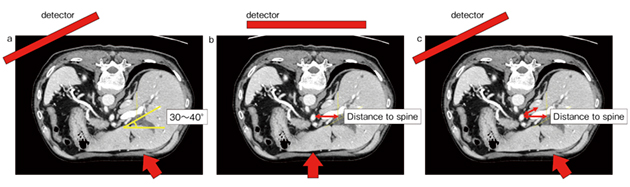

通常、左右の胆管は約30°〜40°傾いているため、Cアームを回転させることで正面視できる(図6 a)。一方、背骨に対して正面視した場合は、左右の合流部と背骨の間には距離があるが(図6 b)、Cアームを斜めに傾けると距離が短くなる(c)。特にCアームを回転させ、左右胆管の分岐を明瞭に描出しようとすると、左胆管は背骨と重なる部分が多くなる。そのため、Cアームの角度は症例に応じて判断する必要がある。

図6 症例3:左右胆管の位置とCアームの角度